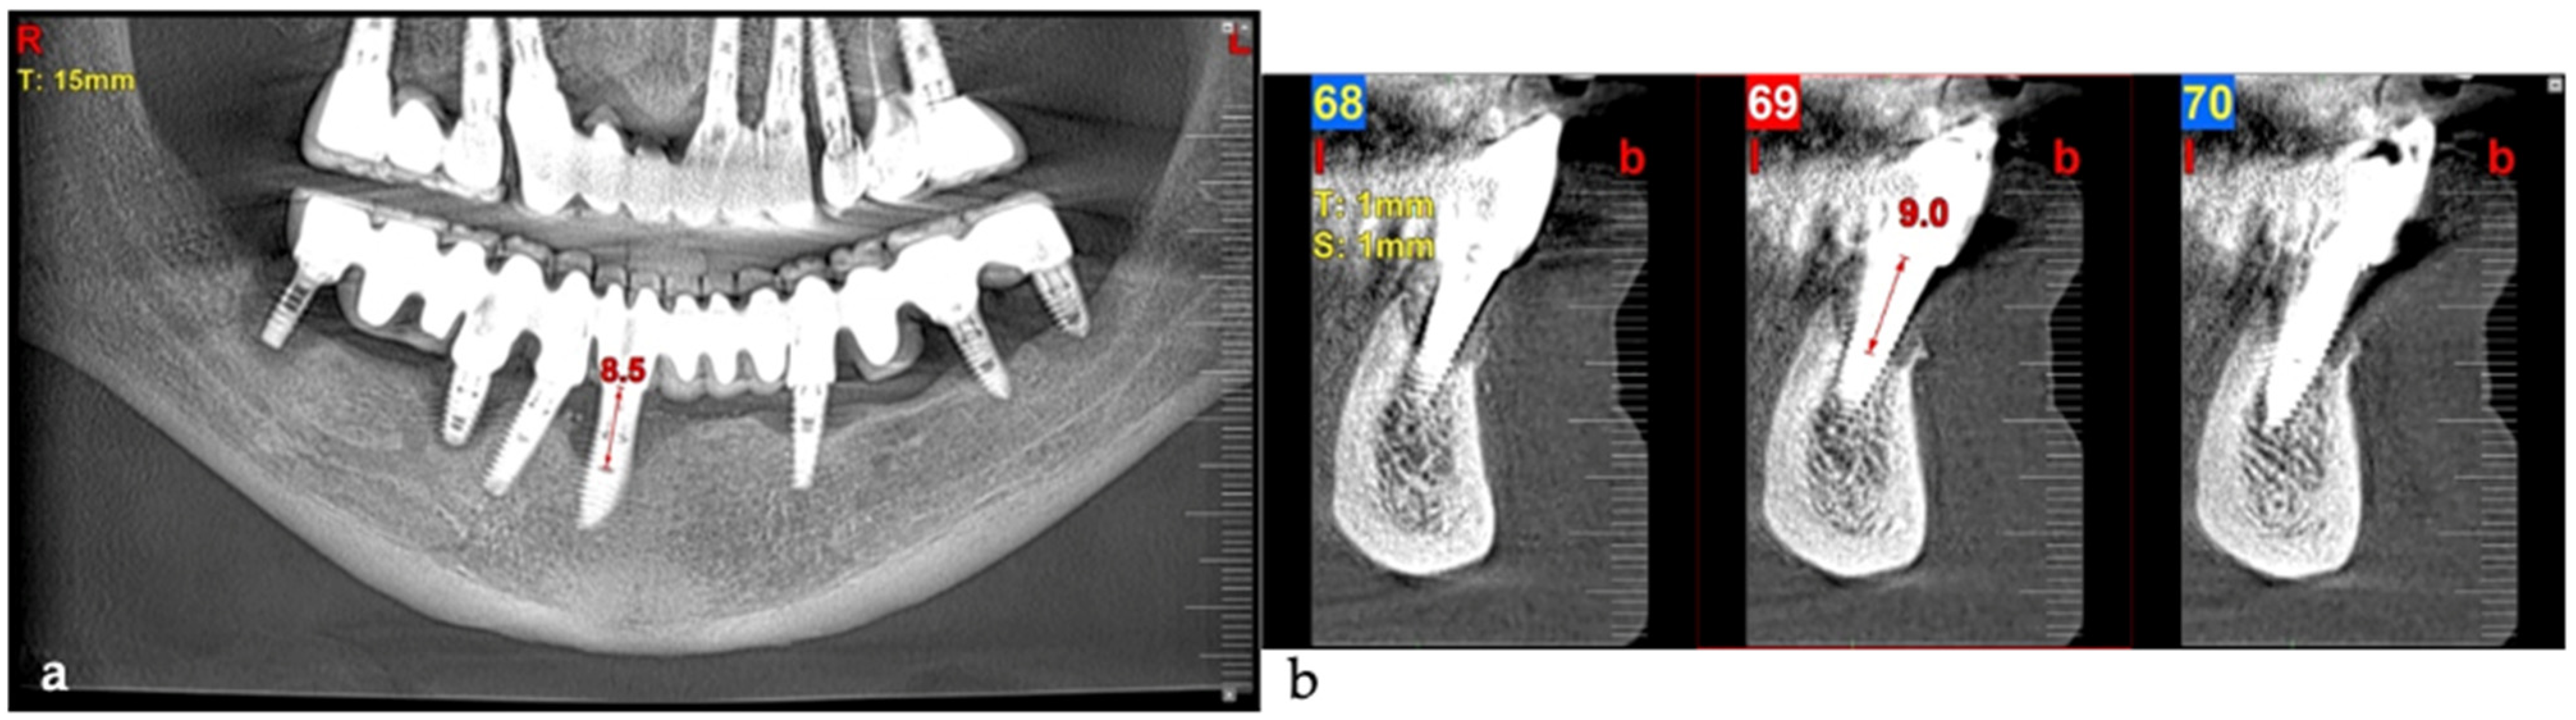

An 80-year-old male patient presented at the private dental office with severe mandibular pain, swelling, and mobility of a dental prosthesis retained by implants. The chief complaint was the lack of stability and mobility in mandible rehabilitation, with the symptoms already described. The medical history included controlled hypertension, hypercholesterolemia, anticoagulant therapy, and a history of heavy tobacco use, which ceased 15 years prior to the oral rehabilitation. The clinical examination revealed inadequate oral hygiene, extensive fixed-prosthesis and dental implant mobility, with PDs exceeding 10 mm; significant BoP was found, and severe vertical bone loss was radiographically confirmed around implant #33, #36, #37, #41, #43, #44, and #47 (Figure 16).

Figure 16. Panoramic radiographic view (a) and cone-beam computed tomography (CBCT) (b), revealing bone loss at baseline at tooth #41, respectively, 8.5 mm and 9.0 mm (red arrows).